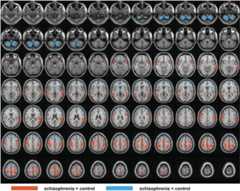

Tables 2 and3 summarize the main findings in the group comparisons. Hyper-connectivity (Table 2) and hypo-connectivity (Table 3) between thalamic sub-regions and various cortical areas were detected in schizophrenia patients compared to controls, which include both primary targets and other regions (non-primary, shaded inTables 2 and3) of each seed. Hyper-connectivity was observed between all thalamic sub-regions and the sensory/motor cortex and the temporal cortex. Hyper-connectivity to some regions in the parietal cortex was also detected from several thalamic sub-regions. Hypo-connectivity in schizophrenia patients was found between thalamic sub-regions and the frontal cortex, the cingulate cortex, the caudate and putamen, and the cerebellum. Most of these changes were detected in both hemispheres in corresponding regions, although the cluster sizes varied between the left and right hemispheres in some regions.Figure 2 displays the regions with significantly decreased or increased thalamic functional connectivity in schizophrenia patients compared to controls on MNI normalized anatomical images (significant regions from each sub-thalamic seed combined on the same figure).

Figure 2.

Map of thalamic functional connectivity changes between schizophrenia patients and control subjects overlaid on MNI normalized anatomical images. Only voxels that show significant difference between the two groups are highlighted (red: schizophrenia > control; blue: schizophrenia < control). Significant results from all sub-thalamic seed regions inTables 2 and3 are shown on the same figure.